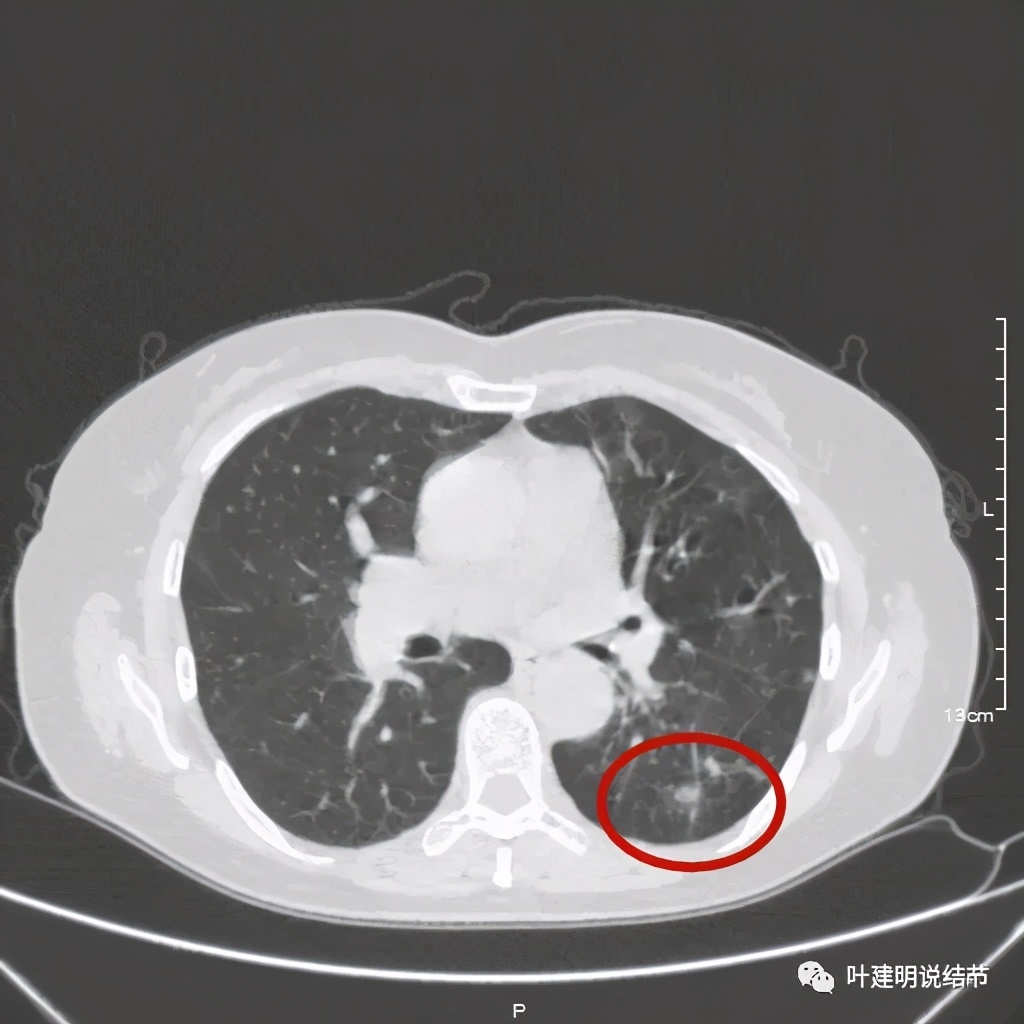

上层见病灶偏实性密度,边缘不光滑

上图见病灶为实性,中间有小空洞,边上有血管进入病灶,靠后侧有棘突样

上图示病灶边缘不光滑,中间有小空洞

上图见病灶边上有血管

上图示病灶血管征较明显,有微小血管从不同方向走向病灶